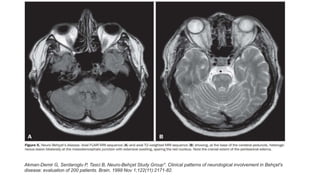

• CSF- leukocytosis (1–360), raised protein.

• MRI hyperintense T2-weighted images in the brainstem, thalamus

,internal capsule and cerebellum

Akman-Demir G, Serdaroglu P, Tasci B, Neuro-Behçet Study Group*. Clinical patterns of neurological involvement in Behçet's

disease: evaluation of 200 patients. Brain. 1999 Nov 1;122(11):2171-82.